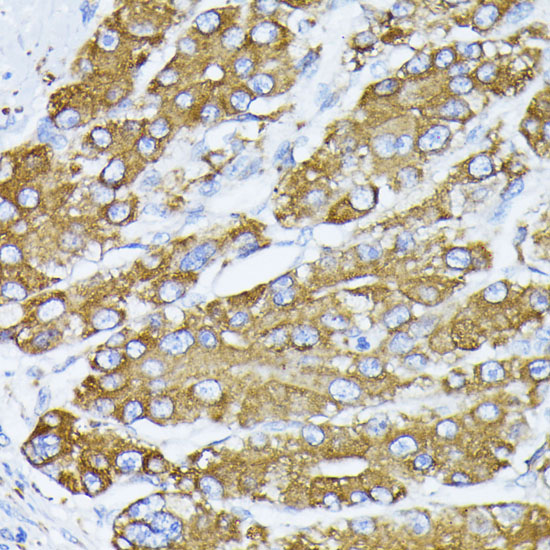

BackgroundThe protein encoded by this gene is a member of the heat shock protein 70 (HSP70) family. It is localized in the lumen of the endoplasmic reticulum (ER), and is involved in the folding and assembly of proteins in the ER. As this protein interacts with many ER proteins, it may play a key role in monitoring protein transport through the cell.

DescriptionGRP78-BiP Polyclonal Antibody. Unconjugated. Raised in: Rabbit.

ImmunogenA synthetic peptide corresponding to a sequence within amino acids 550-650 of human GRP78 / BiP (NP_005338.1)

Alternative NamesHSPA5; BIP; GRP78; HEL-S-89n; MIF2; 78 kDa glucose-regulated protein

ApplicationWB, IHC